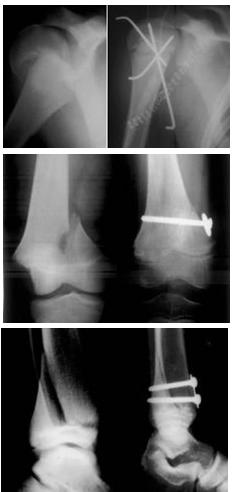

Il trattamento nei distacchi senza spostamento prevede solo la tutela in apparecchio gessato. Nei distacchi con spostamento è invece necessaria una precoce riduzione con manovre delicate cercando di ottenere l’ottimale ripristino dell’anatomia epifisio-metafisaria. In alcuni casi va applicata trazione transcheletrica che sarà inglobata nell’apparecchio gessato.

Nelle lesioni non riducibili si ricorre alla riduzione cruenta e alla sintesi di minima (i mezzi di sintesi, fili o viti, andranno rimossi precocemente).

In tutti i casi fondamentale risulta una buona riduzione ed adeguata immobilizzazione.